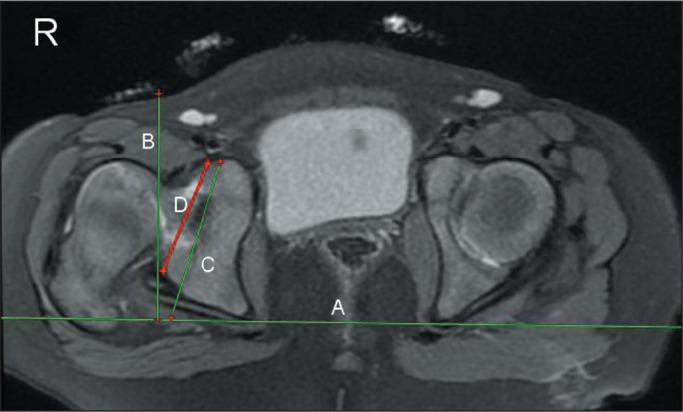

This was a cross-sectional study of 20 consecutive patients with DDH (27 dysplastic hips) who were examined with MRI. In dysplastic and normal hips (DDH and comparison groups, respectively), we evaluated the following parameters: osseous acetabular anteversion (OAA); cartilaginous acetabular anteversion (CAA); femoral anteversion; osseous Mckibbin index (OMI); cartilaginous Mckibbin index (CMI); and the thickness of the anterior and posterior acetabular cartilage.

材料与方法

这是一项对20例连续的DDH患者(27个发育不良髋关节)进行MRI检查的横断面研究。在发育不良髋关节和正常髋关节(分别为DDH组和对照组)中,我们评估了以下参数:骨性髋臼前倾角(OAA);软骨性髋臼前倾角(CAA);股骨前倾角;骨性麦基宾指数(OMI);软骨性麦基宾指数(CMI);以及髋臼前后软骨的厚度。

结果

发育不良髋关节的OAA显著更大。正常髋关节和发育不良髋关节之间的CAA、股骨前倾角、OMI和CMI无显著差异。在DDH组和对照组中,OAA显著低于CAA,OMI显著低于CMI,髋臼后软骨显著厚于前软骨。